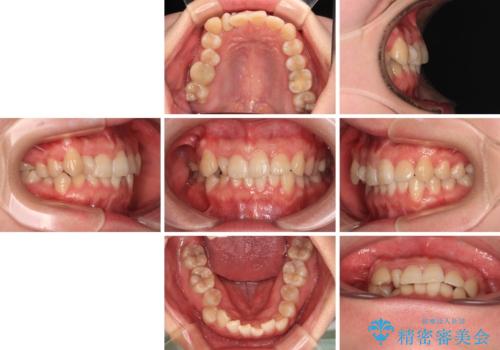

捻転の強い前歯 ワイヤー装置での非抜歯矯正

- 20代女性

- 治療期間

- 1年7ヶ月

- 前歯のデコボコ、特に90度捻れている上顎前歯を気にして来院された患者様です。

マウスピースでもワイヤーでも対応可能でしたら、捻転が非常に強いことから、患者様と相談の上ワイヤー装置にて矯正治療を行うこととしました。

捻転を解消する際に、歯列全体が前方に突出して出っ歯の仕上がりとなることが懸念されたため、補助装置を用いて上顎歯列全体を後方に移動する力をかけることとしました。

適合や携帯の悪いプラスチックのクラウンが装着されていたため、矯正治療後にオールセラミッククラウンによる補綴治療を行うこととしました。

当初予定通り1年半ほどの治療期間で、非常に綺麗な歯列に仕上げることができました。